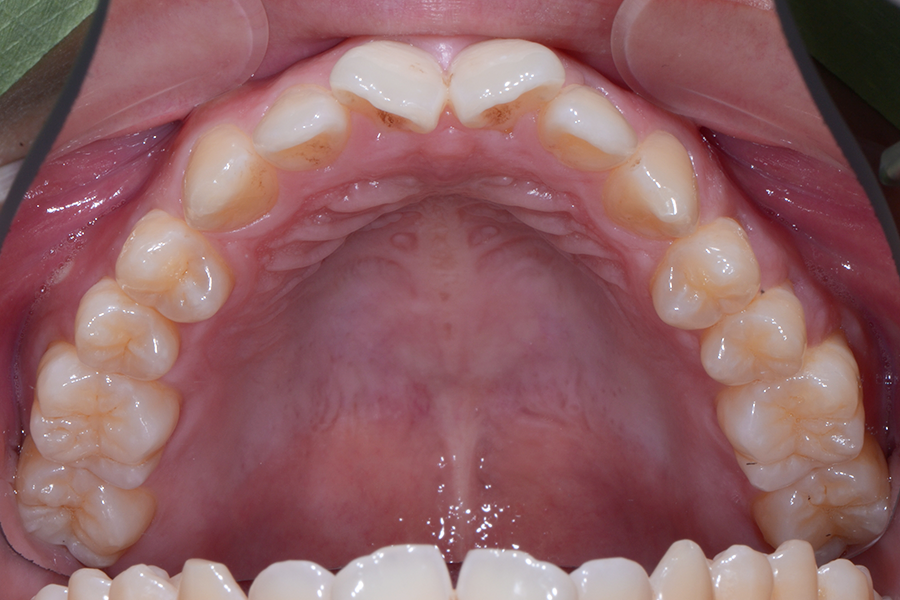

• 治療後